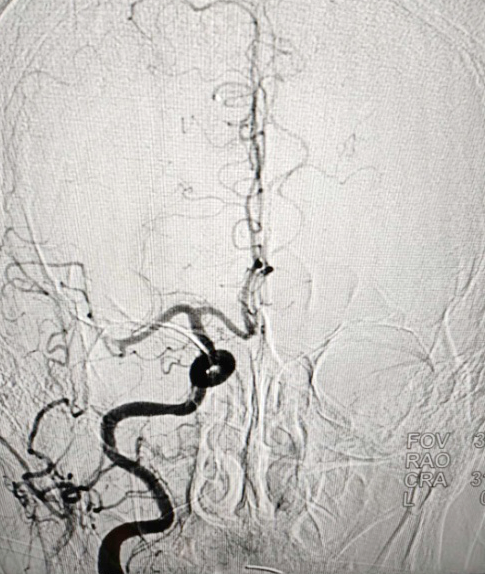

▲取栓前造影提示右侧大脑中动脉M1段远端闭塞

72岁的刘大爷,在家突然意识不清,出现偏瘫,失语的症状,家人发现后立即送往我院。紧急救援中心医师见患者失语、偏瘫,迅速进行病史询问、体格检查、化验及颅脑CT检查等措施,同时初步考虑急性脑栓塞。后经NIHSS(美国国立卫生研究院卒中量表)评分得出21分(正常人0分,最高值42分)。

刘大爷入院时已经错过最佳的静脉溶栓时间,根据患者的症状,神经外科二病区神经介入脑血管病诊疗团队快速评估病情,紧急讨论后决定为患者急行“脑血管造影+抽吸取栓术”。

▲术中情况

治疗脑梗塞主要有溶栓和取栓两种方式。对取栓而言,有相对较长的时间窗,即发病到开始取栓的时间段,最长可达24小时,但最好是控制在6小时之内,这样才能获得最好的治疗效果,而患者的发病时间恰好在这个时间范围内,为取栓赢得了宝贵的手术机会。经过积极的准备后,手术在康宏达主任的指导下,由脑血管病介入团队冉军民、姜正辕、卢永强主治医师顺利完成。术后,患者的右侧大脑中动脉开通,血流恢复,TICI 3级,NIHSS评分10分,症状改善,手术取得圆满成功。